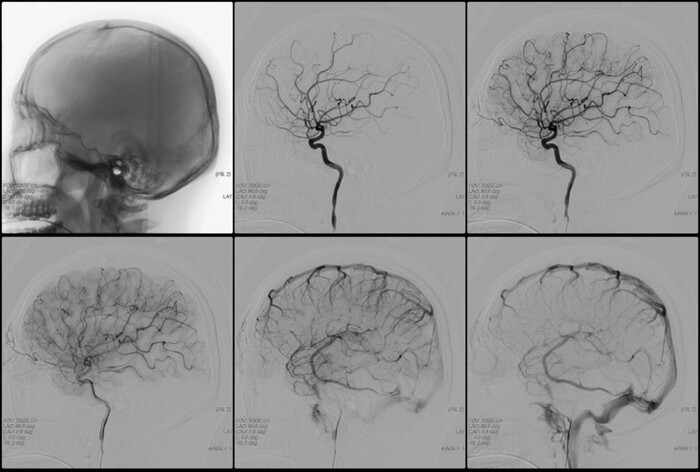

Учтите, что во-первых, сосуды расположены всегда индивидуально и чем они мельче, тем более рандомно, а во-вторых, сеть сосудов здесь изображена условно и, на самом деле, выглядит как-то так:

Это, ИМХО, основной фактор облысения, а вовсе не дигидротестостерон. Хотя, напоминаю, я не доктор.